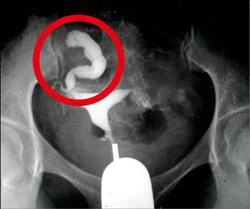

ㄒ輸卵管積水像香腸切掉輸卵管,博元婦產科試管嬰兒一次成功! https://www.youtube.com/watch?v=cwBEl4M4CZ4 輸卵管積水要不要先切掉積水的輸卵管? 來增加試管嬰兒成功率, 或者這樣...